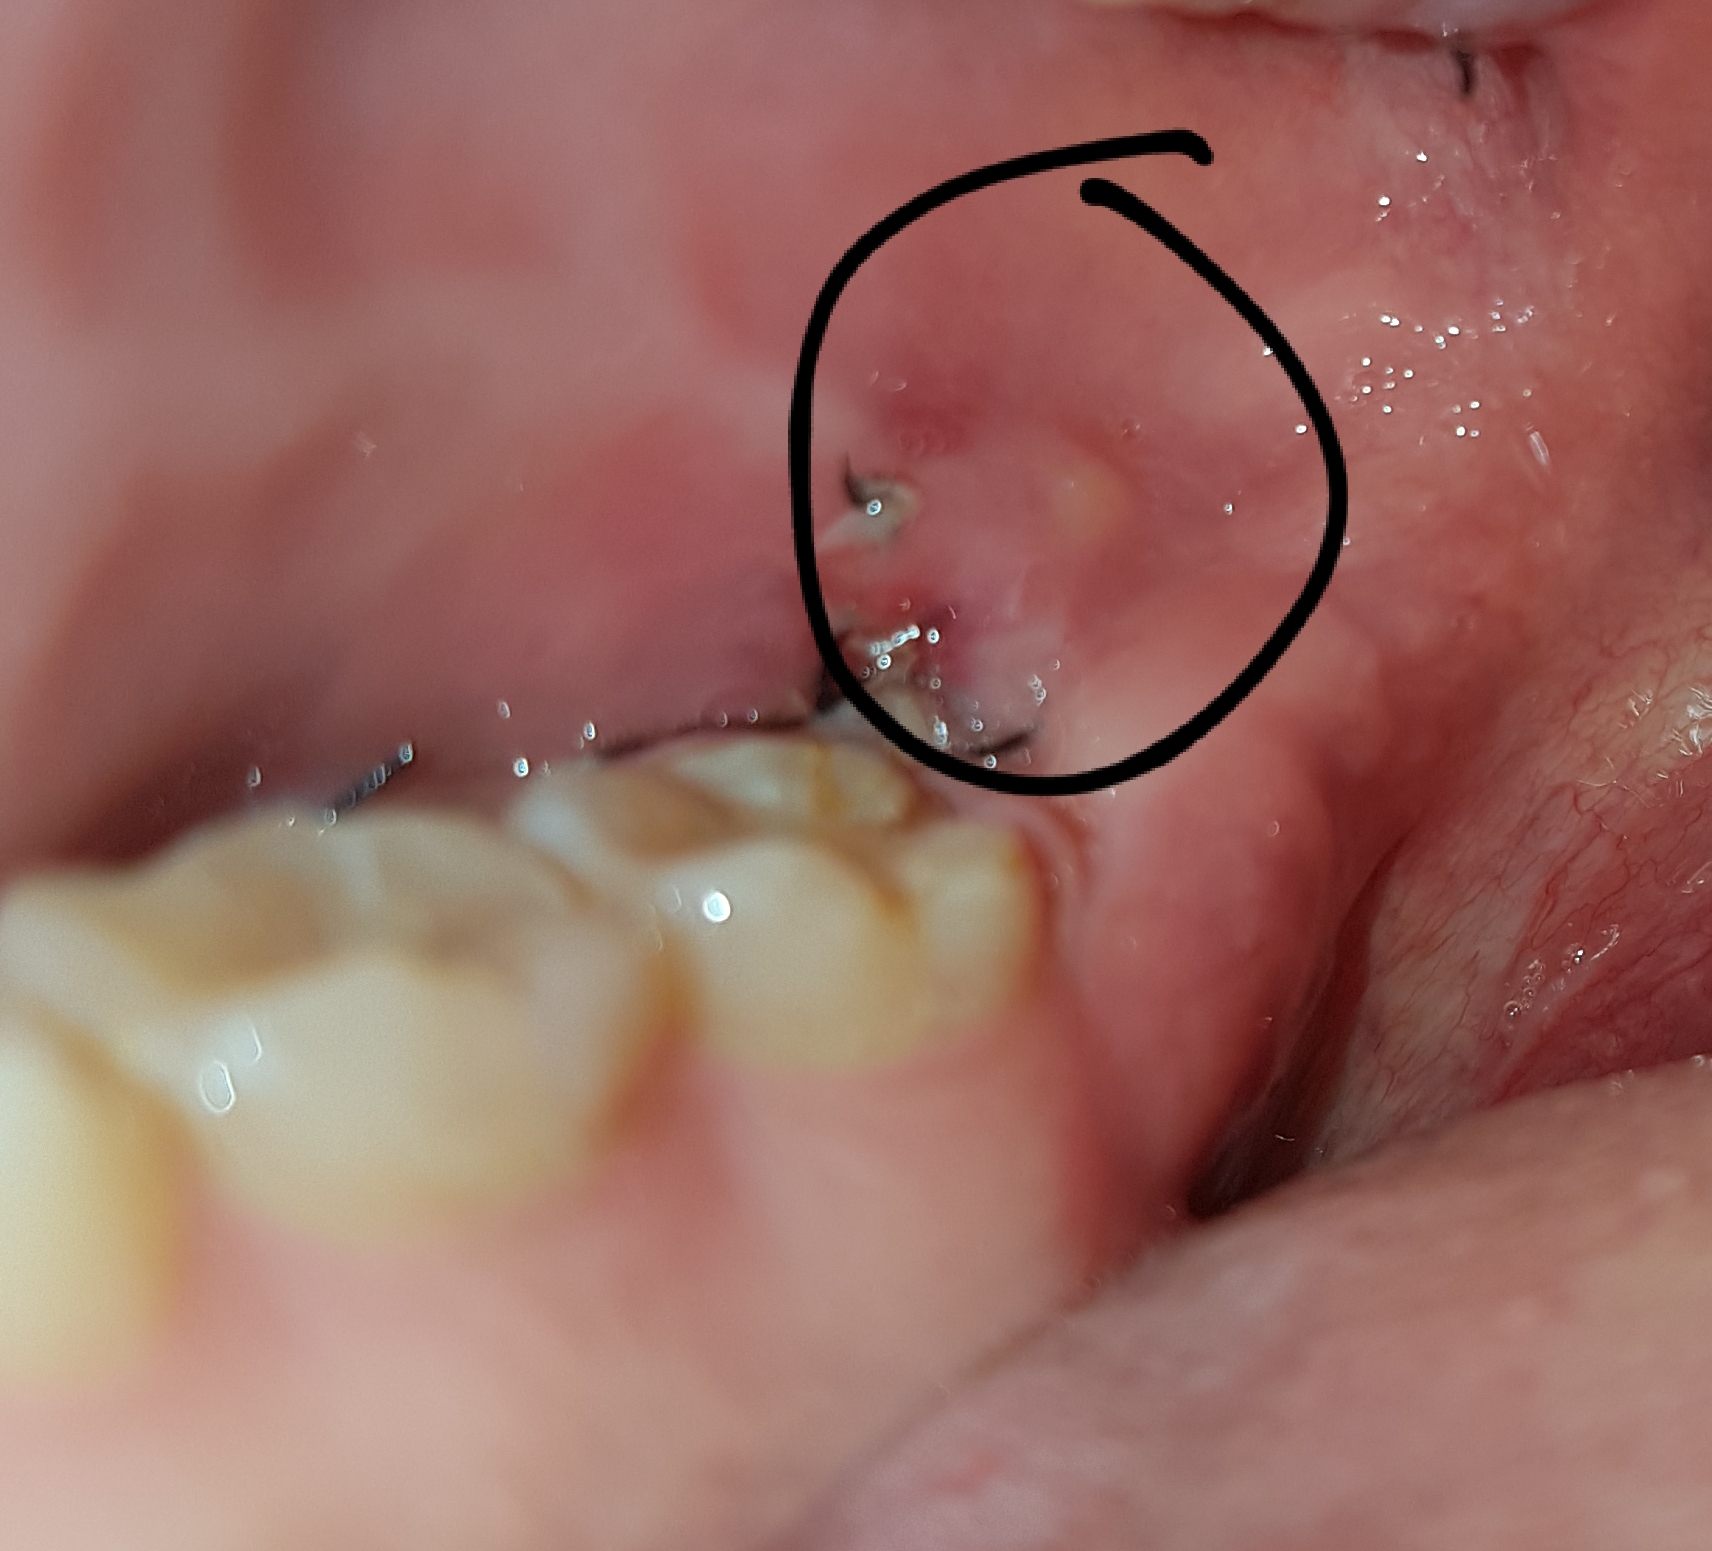

Tag 5 nach der Weisheitszahn-OP: Der Blut-Blues

Und hier kommt der Knackpunkt. Sagen wir mal, es ist Tag 5. Du denkst, du bist über den Berg. Du hast deine Schmerzmittel brav geschluckt, deine Mundspülung fleißig benutzt und sogar versucht, ein bisschen zu lächeln (was ehrlich gesagt mehr wie ein Grimasse aussieht).

Und dann… Blut. Plötzlich, ohne Vorwarnung, ist da wieder dieses kleine, fiese Rinnsal. Was zur Hölle, denkst du. Sollte das nicht längst vorbei sein?

Die üblichen Verdächtigen: Warum blutet es immer noch?

Okay, okay, ich will ja nicht komplett zynisch sein. Es gibt natürlich *logische* Erklärungen. Vielleicht hast du zu viel gemacht. Vielleicht hast du dich zu doll geschnäuzt (Ja, das ist ein Ding! Wer hätte das gedacht?). Vielleicht hast du einfach Pech. Die Blutgerinnung ist halt manchmal eine Diva.

Und natürlich gibt es die gefürchtete Alveolitis. Das böse A-Wort, das jeden Weisheitszahn-Patienten in Angst und Schrecken versetzt. Ich will es jetzt nicht zu sehr beschwören, aber wenn du *wirklich* starke Schmerzen hast, die nicht besser werden, und der Geruch aus deinem Mund einem Klärwerk gleicht, dann… ja, dann solltest du vielleicht doch mal deinen Zahnarzt anrufen.